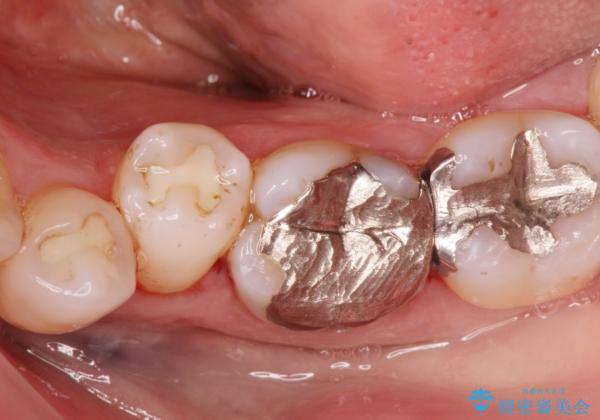

[銀歯の下が虫歯に] ジルコニアクラウンで修復

- 銀歯の下が虫歯になっていたので拡大鏡下で虫歯を取り除き、ジルコニアクラウンで治療を行いました。

白く適合の良い被せ物が入りました。

現在他の部位も検討中です。